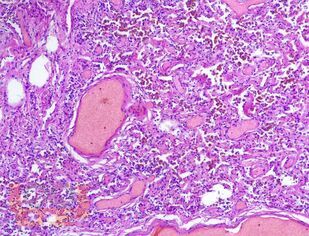

В учебном пособии представлен теоретический материал, перечень макропрепаратов и микропрепаратов, демонстрирующих типовые проявления патологических процессов. В цветных иллюстрациях и в описании микропрепаратов сделан акцент на наиболее важных гистологических изменениях, позволяющих на светооптическом уровне диагностировать и дифференцировать состояния, отклоняющиеся от нормы, в том числе с использованием различных гистологических окрасок. Пособие помогает выделить главные аспекты изучаемых патологических процессов, организовать и конкретизировать учебный процесс.